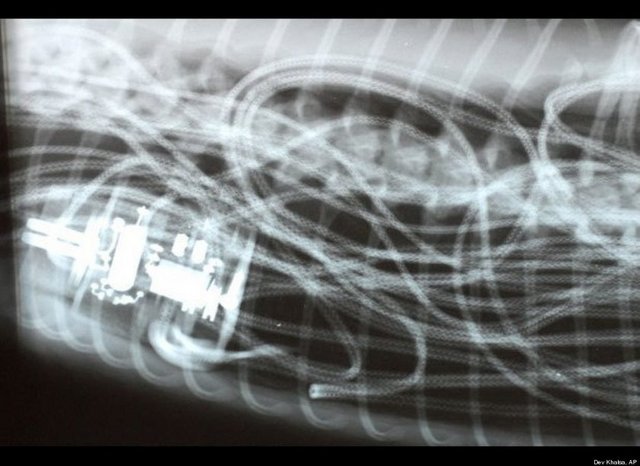

"Özellikle havaalanlarındaki girişlerde iki tür cihazı da görebiliriz. Eşyaların geçirildiği X-Ray cihazında X ışınları kullanılarak görüntüleme yapılır. Çantaların içinde ne olduğu X ışınları ile görüntülenir. Burada uygulanan X ışınlarının eşyalara bir zararı yoktur, birikmez, eşyalarda radyasyon kirliliği yapmaz. Bu cihazların çevresi X ışınlarının insanlara zarar vermemesi için kurşun paravanlarla kaplıdır."